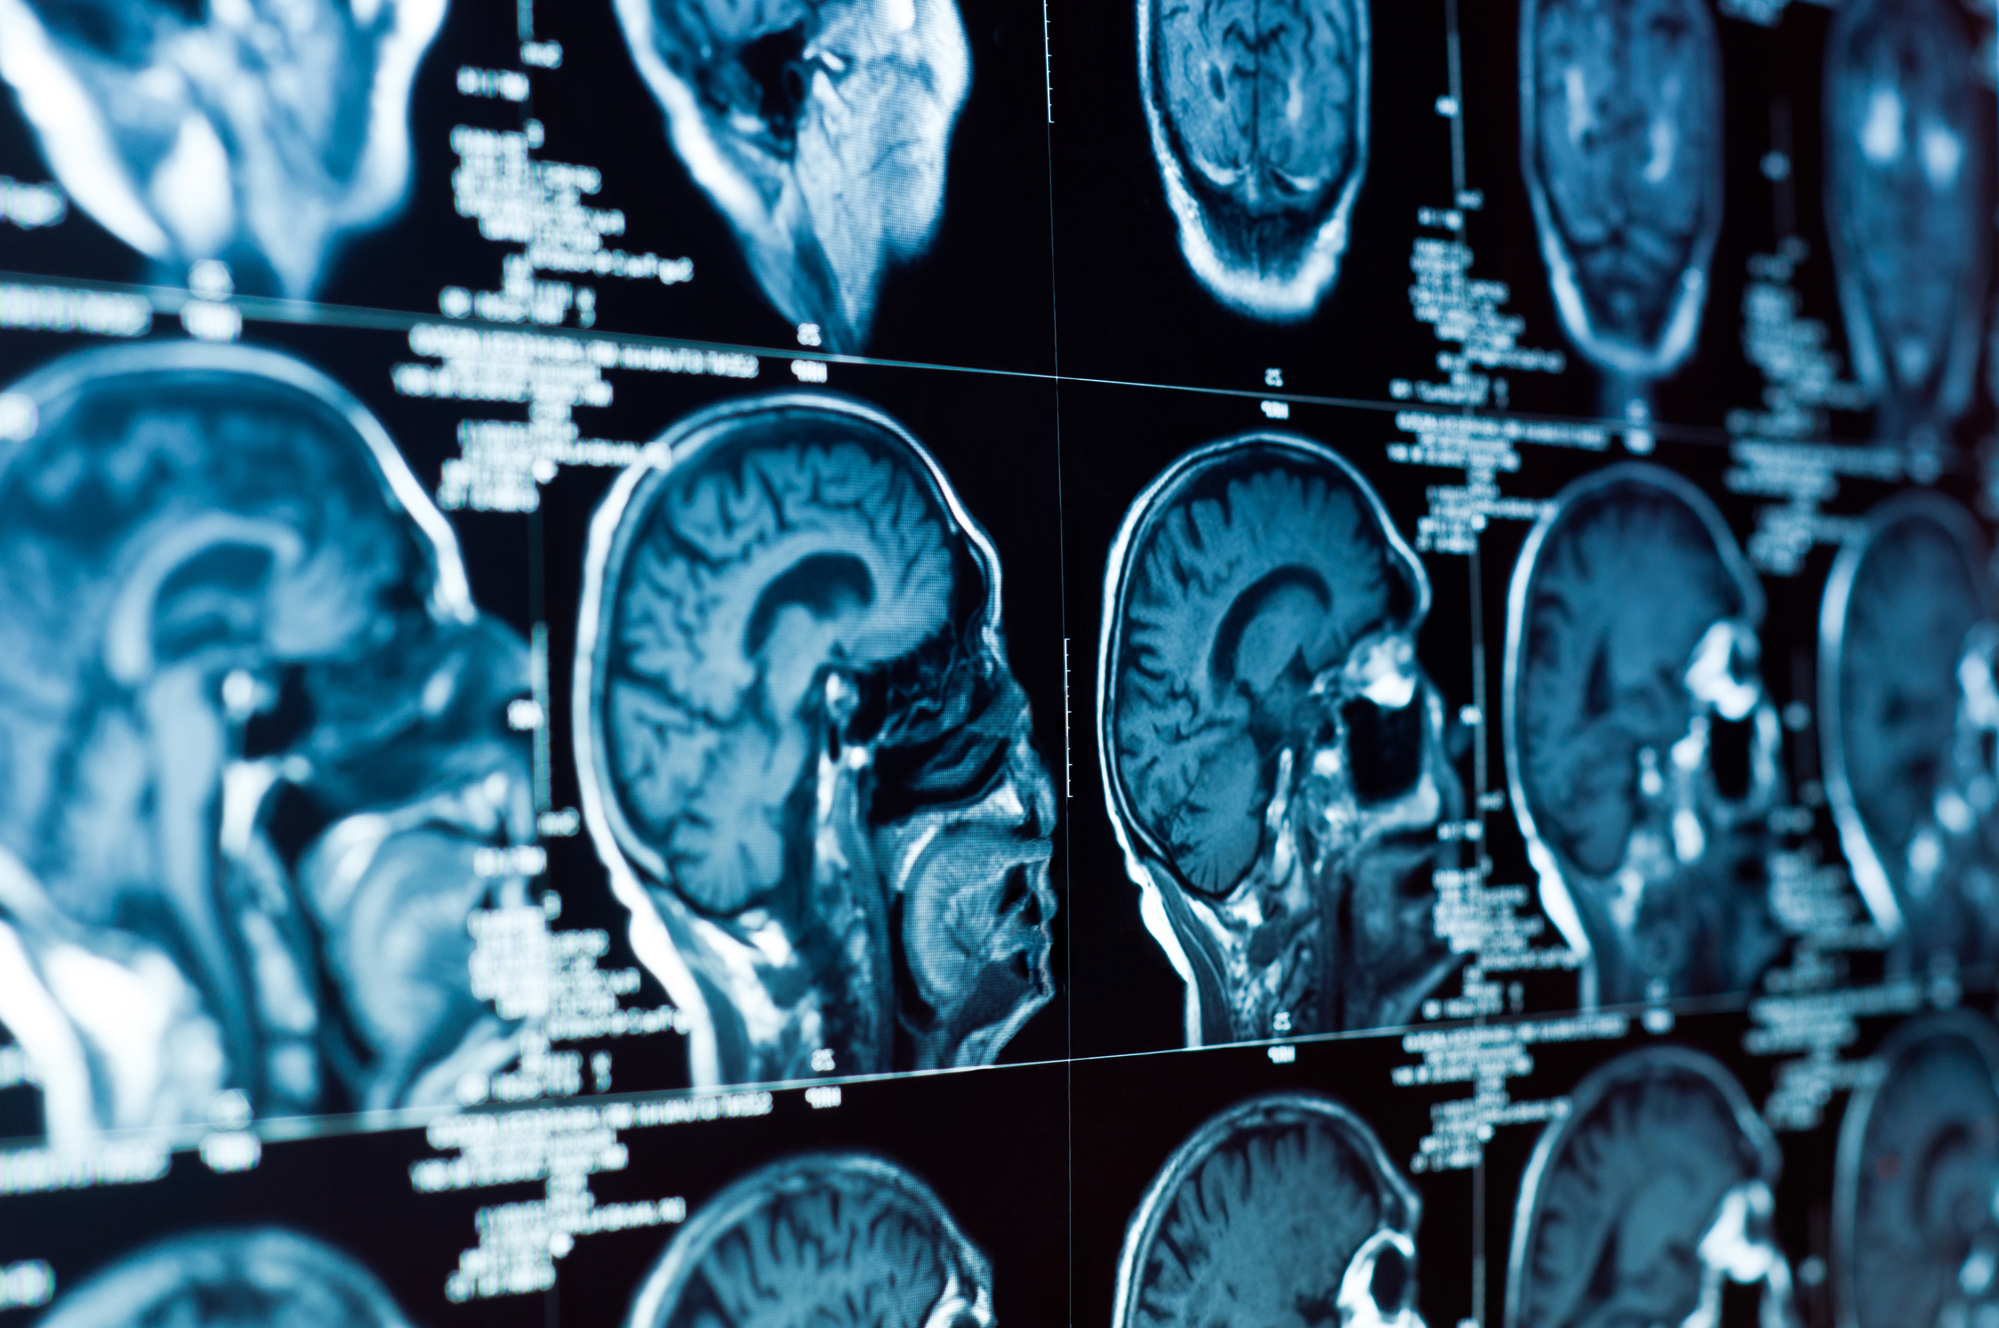

A brain scan

Closeup of a CT scan of the brain and skull. Deposit Photos